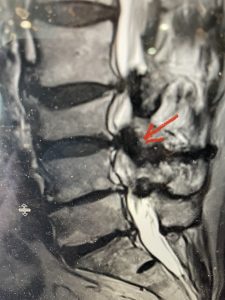

(Figs 5a): Sagittal (a) and axial (b) T2-weighted lumbar MRI demonstrating status post lumbar decompression and insitu fusion L2-5 now well decompressed (blue dash) with development of new (red arrow) severe stenosis and with superimposed right L1-2 disc herniation (blue arrow)

(Figs 5b)